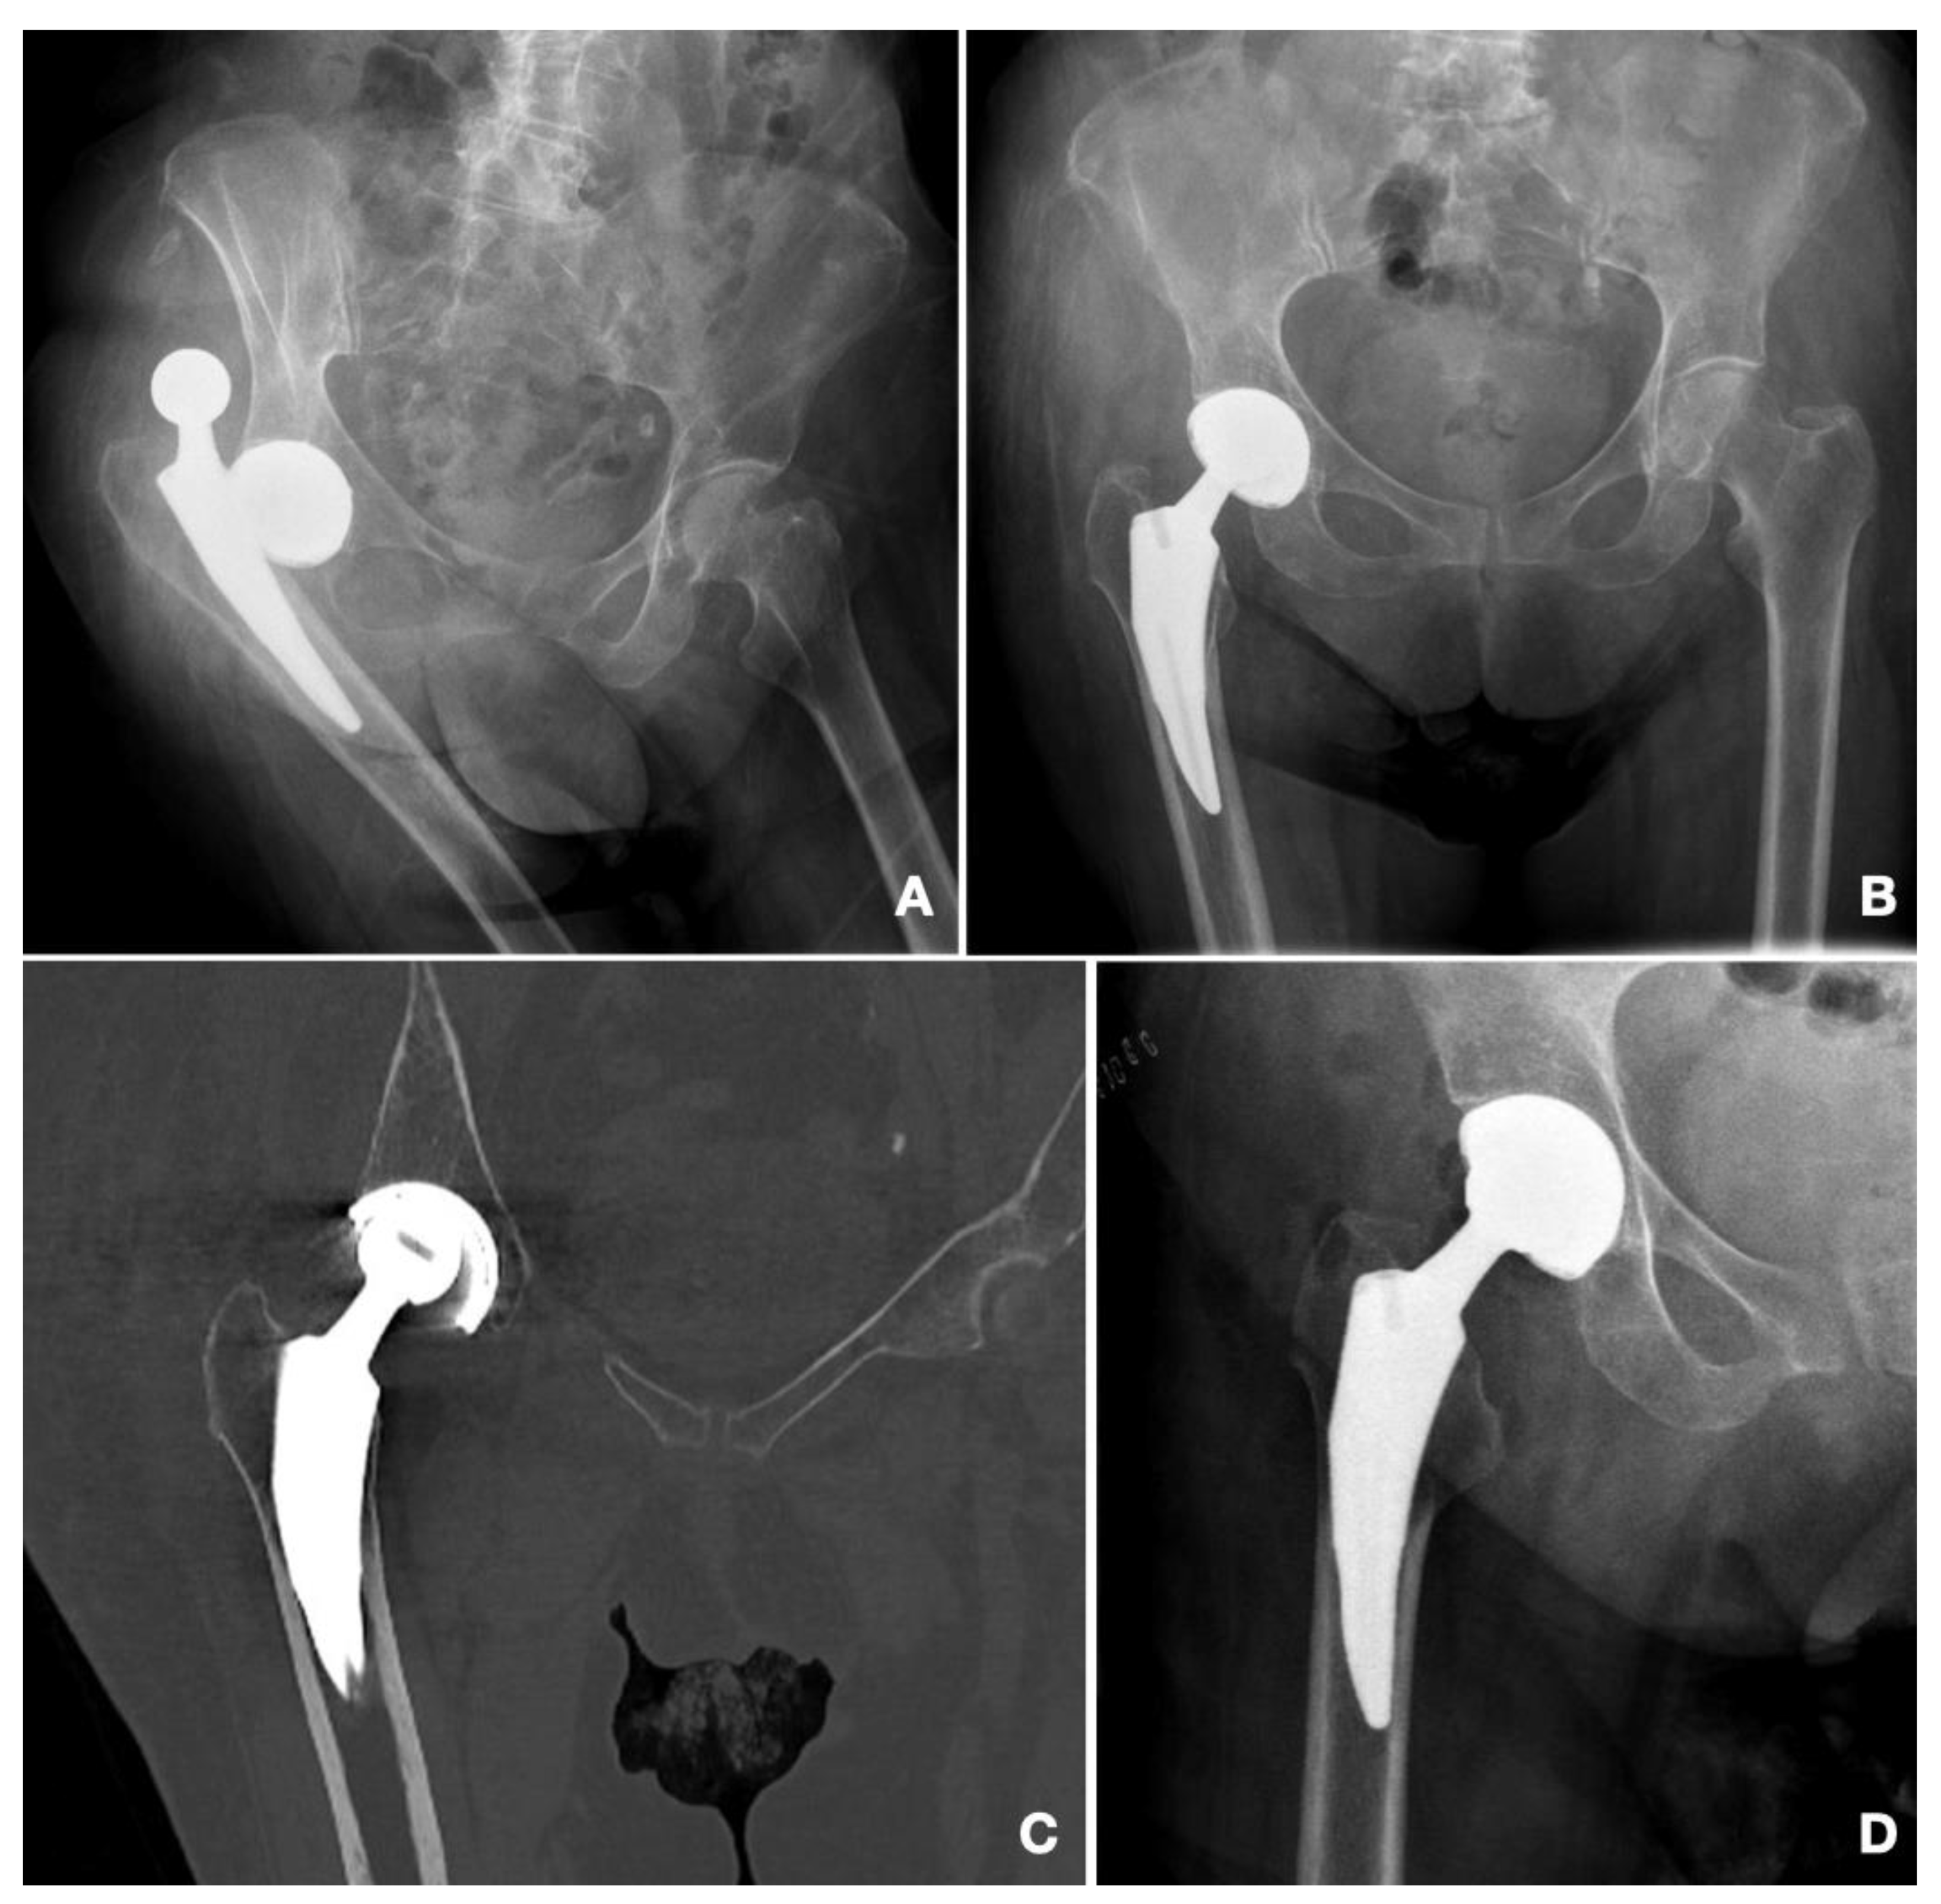

| ID | Cup | Time after Index Surgery | Mechanism | Reduction | Redislocation | Remarks | Need for Revision | Functional Status (Parker) |

|---|---|---|---|---|---|---|---|---|

| 1 | G7 | 5 | Atraumatic | Closed | - | No | Walks with one simple aid | |

| 2 | G7 | 45 | Atraumatic | Closed | 26 days after | Death < 1 year | No | Walks with walking frame |

| 3 | G7 | 1 | Atraumatic | Open | 4 days after | Death < 1 year | 1st episode: Stem and Cup revision 2nd episode: Girdlestone | No walking |

| 4 | Apogee | 13 | Traumatic | Open | No walking | |||

| 5 | G7 | 6 | Atraumatic | Closed | 1 day after 9 days after | 2nd episode: Cup revision 3rd episode: Cup revision | No walking | |

| 6 | G7 | 72 | Atraumatic | Closed | Walks with one simple aid | |||

| 7 | G7 | 376 | Traumatic | Open | Intraprosthetic dislocation | Revision of dual mobility head | Walks with walking frame | |

| 8 | G7 | 23 | Atraumatic | Open | Dislocation associated with Vancouver B2 fracture | Revision of stem | Walks with one simple aid |